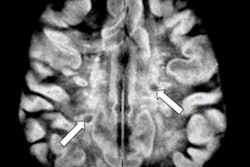

Axial T2-weighted image (a) shows an intermediate signal intensity tumor (arrow), measuring 3 cm, with central necrosis and invasion of the external urethral meatus (arrowhead) -- FIGO II. On diffusion-weighted imaging, the tumor is depicted by a high signal intensity lesion (b-value = 1000 s/mm2) (arrow), and low signal intensity on the corresponding ADC map (arrow). On T1WI fat saturation contrast-enhanced sequence (D), the tumor shows early arterial enhancement of its solid component (arrow), with no enhancement of the central necrotic portion. Note the increased conspicuity of the lesion in diffusion-weighted MRI (b) and (c) and in DCE-MRI (d).The new guidelines apply to adults over 18 who have SCC of the vulva and do not address patients with other vulvar cancer histologies.